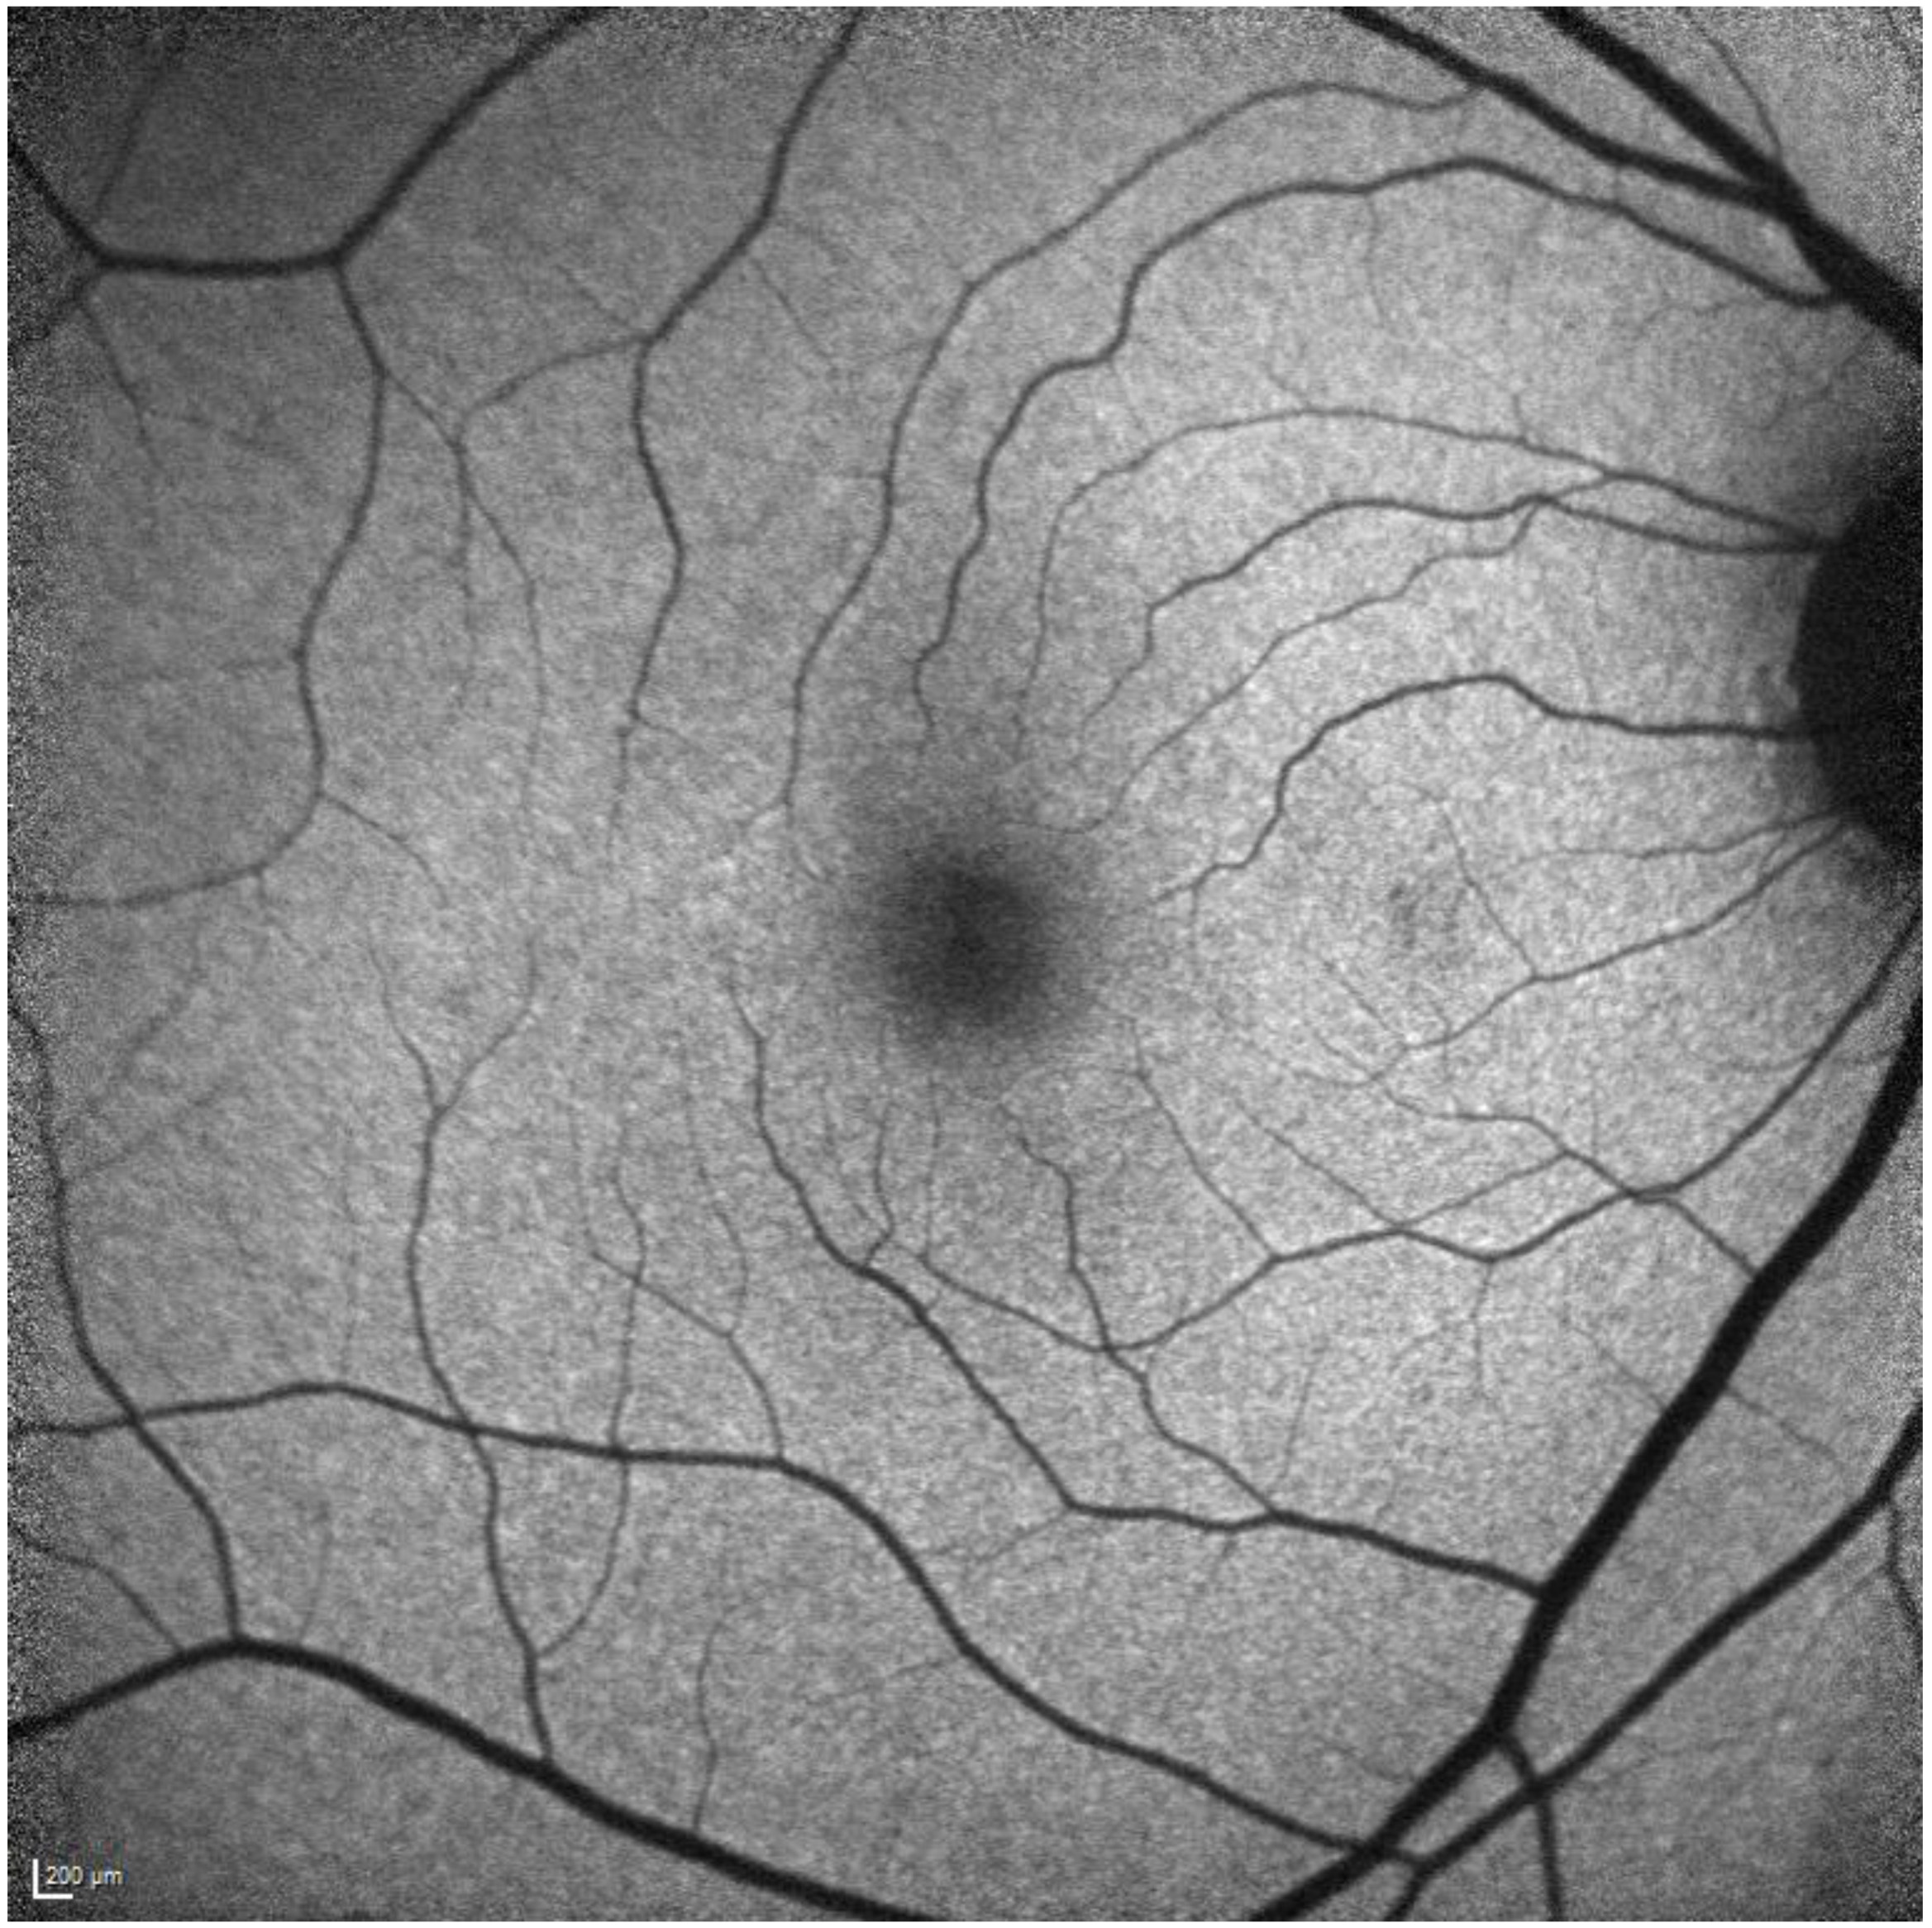

- Ahn, S.J.; Lee, S.U.; Lee, S.H.; Lee, B.R. Evaluation of Retromode Imaging for Use in Hydroxychloroquine Retinopathy. Am. J. Ophthalmol. 2018, 196, 44–52. [Google Scholar] [CrossRef] [PubMed]

- Acton, J.H.; Cubbidge, R.P.; King, H.; Galsworthy, P.; Gibson, J.M. Drusen Detection in Retro-Mode Imaging by a Scanning Laser Ophthalmoscope. Acta Ophthalmol. 2011, 89, e404–e411. [Google Scholar] [CrossRef] [PubMed]

- Giansanti, F.; Mercuri, S.; Serino, F.; Caporossi, T.; Savastano, A.; Rizzo, C.; Faraldi, F.; Rizzo, S.; Bacherini, D. Scanning Laser Ophthalmoscopy Retromode Imaging Compared to Fundus Autofluorescence in Detecting Outer Retinal Features in Central Serous Chorioretinopathy. Diagnostics 2022, 12, 2638. [Google Scholar] [CrossRef]